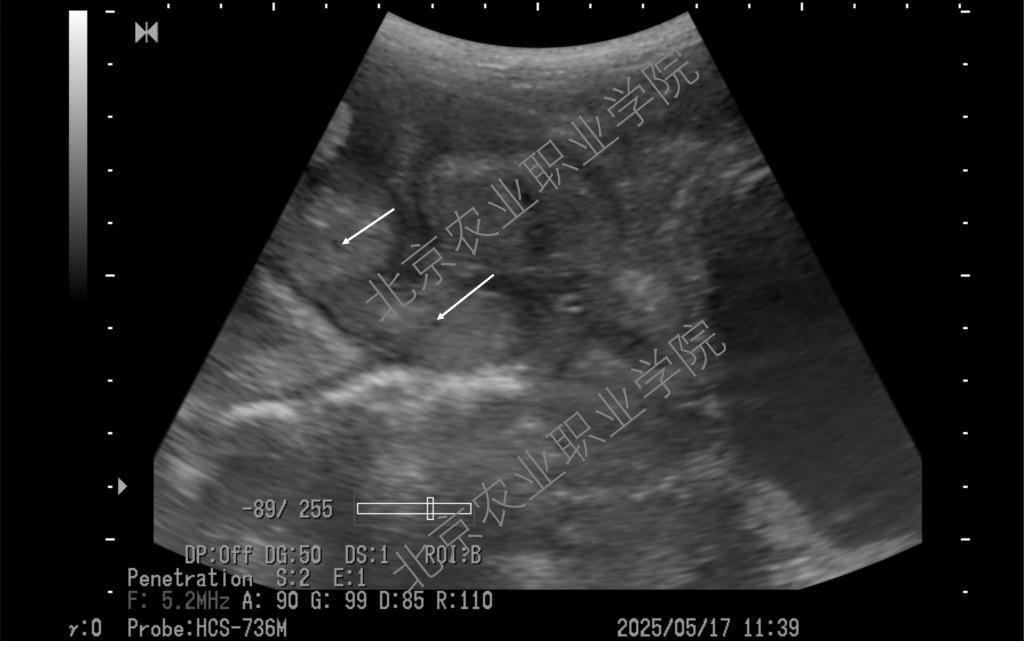

近日,受北京伟杰信生物科技有限公司邀请,动物科技学院兽医超声技术团队为该公司“母猪妊娠21天超声检查技术操作规范”项目提供了重要的技术支撑,并取得重大进展。团队首席专家姜晨副教授梳理了母猪不同体位超声扫查的方法,以便技术人员在不改变母猪体位的情况下做出准确诊断,最大程度上降低怀孕母猪不必要的应激。

近年来,Beat365姜晨副教授领衔的兽医超声技术团队积极推广超声影像技术在多种动物临床中的应用,并取得一系列技术成果。团队持续探索母猪孕早期超声检查的边界,目前最早可在排卵后第9天确认是否怀孕(可见直径约1mm的卵囊液)。此超声检查技术已达到国际前沿水平,为打开母猪孕初相关的科学研究之门提供了一把金钥匙。